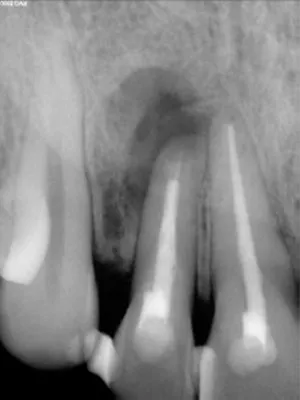

FIG 22:

The X-Ray of the patient after restoration